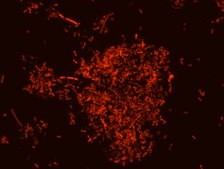

Akkermansia muciniphila probe specifically recognizes Akkermansia muciniphila cells.

FISH technique was successfully used to identify A.muciniphila with the probe in various samples such as pure culture (as described in the figure legends and18), fecal samples 19-21, gut lumen content 22, appendix samples 23, cecum content and tissue24,25 and colon tissue26. The probe can also be used for FISH coupled with flow cytometry (FCM-FISH)19,20,21 and FISH combined with Raman microspectroscopy 24.